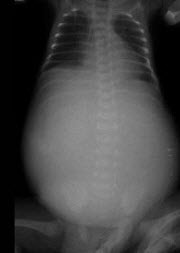

患儿,男,1天,生后呼吸困难,羊水见胎粪污染,如图,最可能的诊断为()

女婴,7月。经常呕吐,腹部饱满、膨隆,消瘦。如图所示,最可能的诊断为()

A.消化道闭锁

B.十二指肠闭锁

C.消化道穿孔

D.肠套叠

E.肠扭转